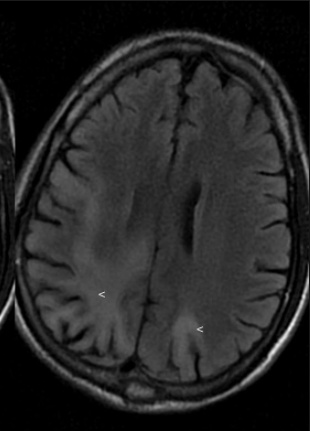

PML: JC virus causes Progressive Multifocal Leukoencephalopathy (PML)

senator count 200 and cane: JC virus reactivated in HIV positive patients with CD4 count <200

white crown leaves: Non-enhancing multifocal brain lesions in white matter (toxoplasma: ring enhancing lesions)

white leaves: white matter affected

peeling legs of table: Leukoencephalopathy is a demyelinating process

pts die in a few months

Nonenhancing:

Enhancing: